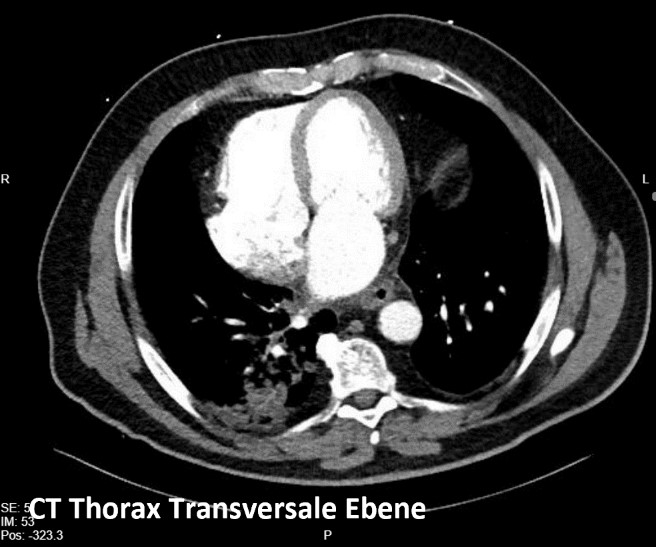

Ein 45-jähriger Patient wurde zur elektiven Kryoballonablation bei persistierendem Vorhofflimmern (EHRA IIa, CHA₂DS₂-VA-Score: 1) aufgenommen. Klinisch zeigte sich im EKG ein überdrehter Rechtstyp (siehe Abb. 1) als Hinweis auf Dextrokardie. Die präinterventionelle CT-Diagnostik (siehe Abb. 2-4) bestätigte die rechtsseitige Herzlage ohne begleitenden Situs inversus. Diese Bildgebung war essenziell für die prä-interventionelle Planung der PVI: Die transseptale Punktion und die Navigation der Katheter erfolgten unter transösophagealer Echokardiographie und angepassten Durchleuchtungsebenen (siehe Abb. 5) mit Beachtung der veränderten räumlichen Orientierung auf Grundlage der CT Diagnostik. Besonders wichtig war dabei die systematische Anpassung der Durchleuchtungs-Ebenen um eine adäquate Darstellung der Pulmonalvenen während der Prozedur zu gewährleisten. Die Kryoablation aller vier Pulmonalvenen erfolgte erfolgreich und komplikationsfrei.

Die erfolgreiche Pulmonalvenenisolation bei Dextrokardie unterstreicht die zentrale Bedeutung einer präzisen Bildgebung mittels CT und transösophagealer Echokardiographie zur Prozedurplanung. Fluoroskopische Orientierungshilfen und Projektionen wurden in diesem Fall bewusst und systematisch auf Grundlage der CT Thorax Diagnostik angepasst, und ermöglichten so eine sichere Navigation und erfolgreiche Ablation. Der vorliegende Fall zeigt, dass auch bei anatomischen Besonderheiten eine Kryo-PVI sicher und effektiv durchführbar ist – vorausgesetzt, die Prozedur wird strukturiert vorbereitet und technisch angepasst.

Abb. 2: